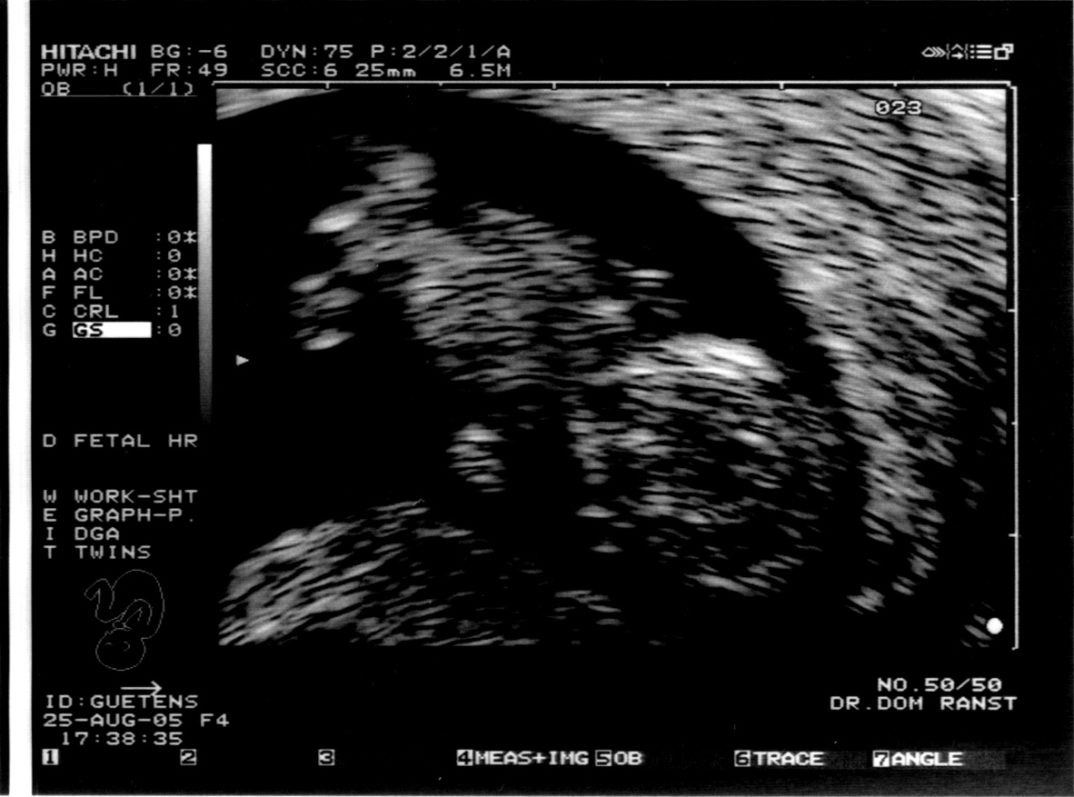

С использованием ультразвукового сканирования, анализа крови и учёта возраста матери проводится комбинированное исследование плода для определения вероятности хромосомной аномалии в онтогенезе, включая синдром Дауна, который является наиболее распространённым. В Исландии, где проживает около 338 тысяч человек по данным на 2017 год, согласно официальной статистике, ежегодно рождаются в среднем два ребенка с синдромом Дауна, чаще всего после того, как их родители получили неточные результаты пренатального скрининга. В соответствии с законодательством Исландии, аборт разрешается до 16 недель беременности в случае подтвержденного наличия деформации у плода.